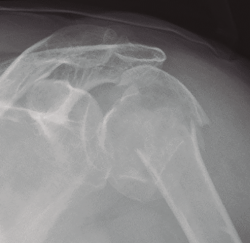

Figura 3. Radiografía simple de fractura glenoidea.

Existen distintos tipos de fracturas escapulares. En ocasiones, tras una fractura glenoidea (35%) (Figura 3), pueden producirse fracturas de coracoides (7%) (Figura 4) y también pueden ocurrir fracturas escapulares indirectas por caídas con la mano extendida(1,3,5).